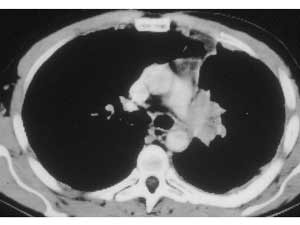

| Figure 9: Line drawing (left) and intraoperative image (right) showing the usual pattern of infiltration of the interlobar portion of the pulmonary artery posterior to the left upper lobe bronchus.* | |

![]() |

During resection control of the main pulmonary artery and the inferior pulmonary vein is obtained. The superior pulmonary vein is divided in a standard fashion. Pulmonary arterial tissue is resected en bloc with the specimen. After the resection, an oval defect oriented along the PA axis remains, even if the resected portion was circular in shape (Figure 10). This is due to the tension applied on the vessel by the lower lobe. The patch should be tailored according to the size and shape of the resected portion rather than according to the PA defect (Figure 11). After the patch is secured to the artery by 5/0 or 6/0 monofilament running suture, the PA is declamped (Figure 12). The suture line must be checked carefully for oozing, which might not be evident due to the low PA pressure. Also it is important to check the position of the artery after reexpansion of the lower lobe, for kinking might occur.